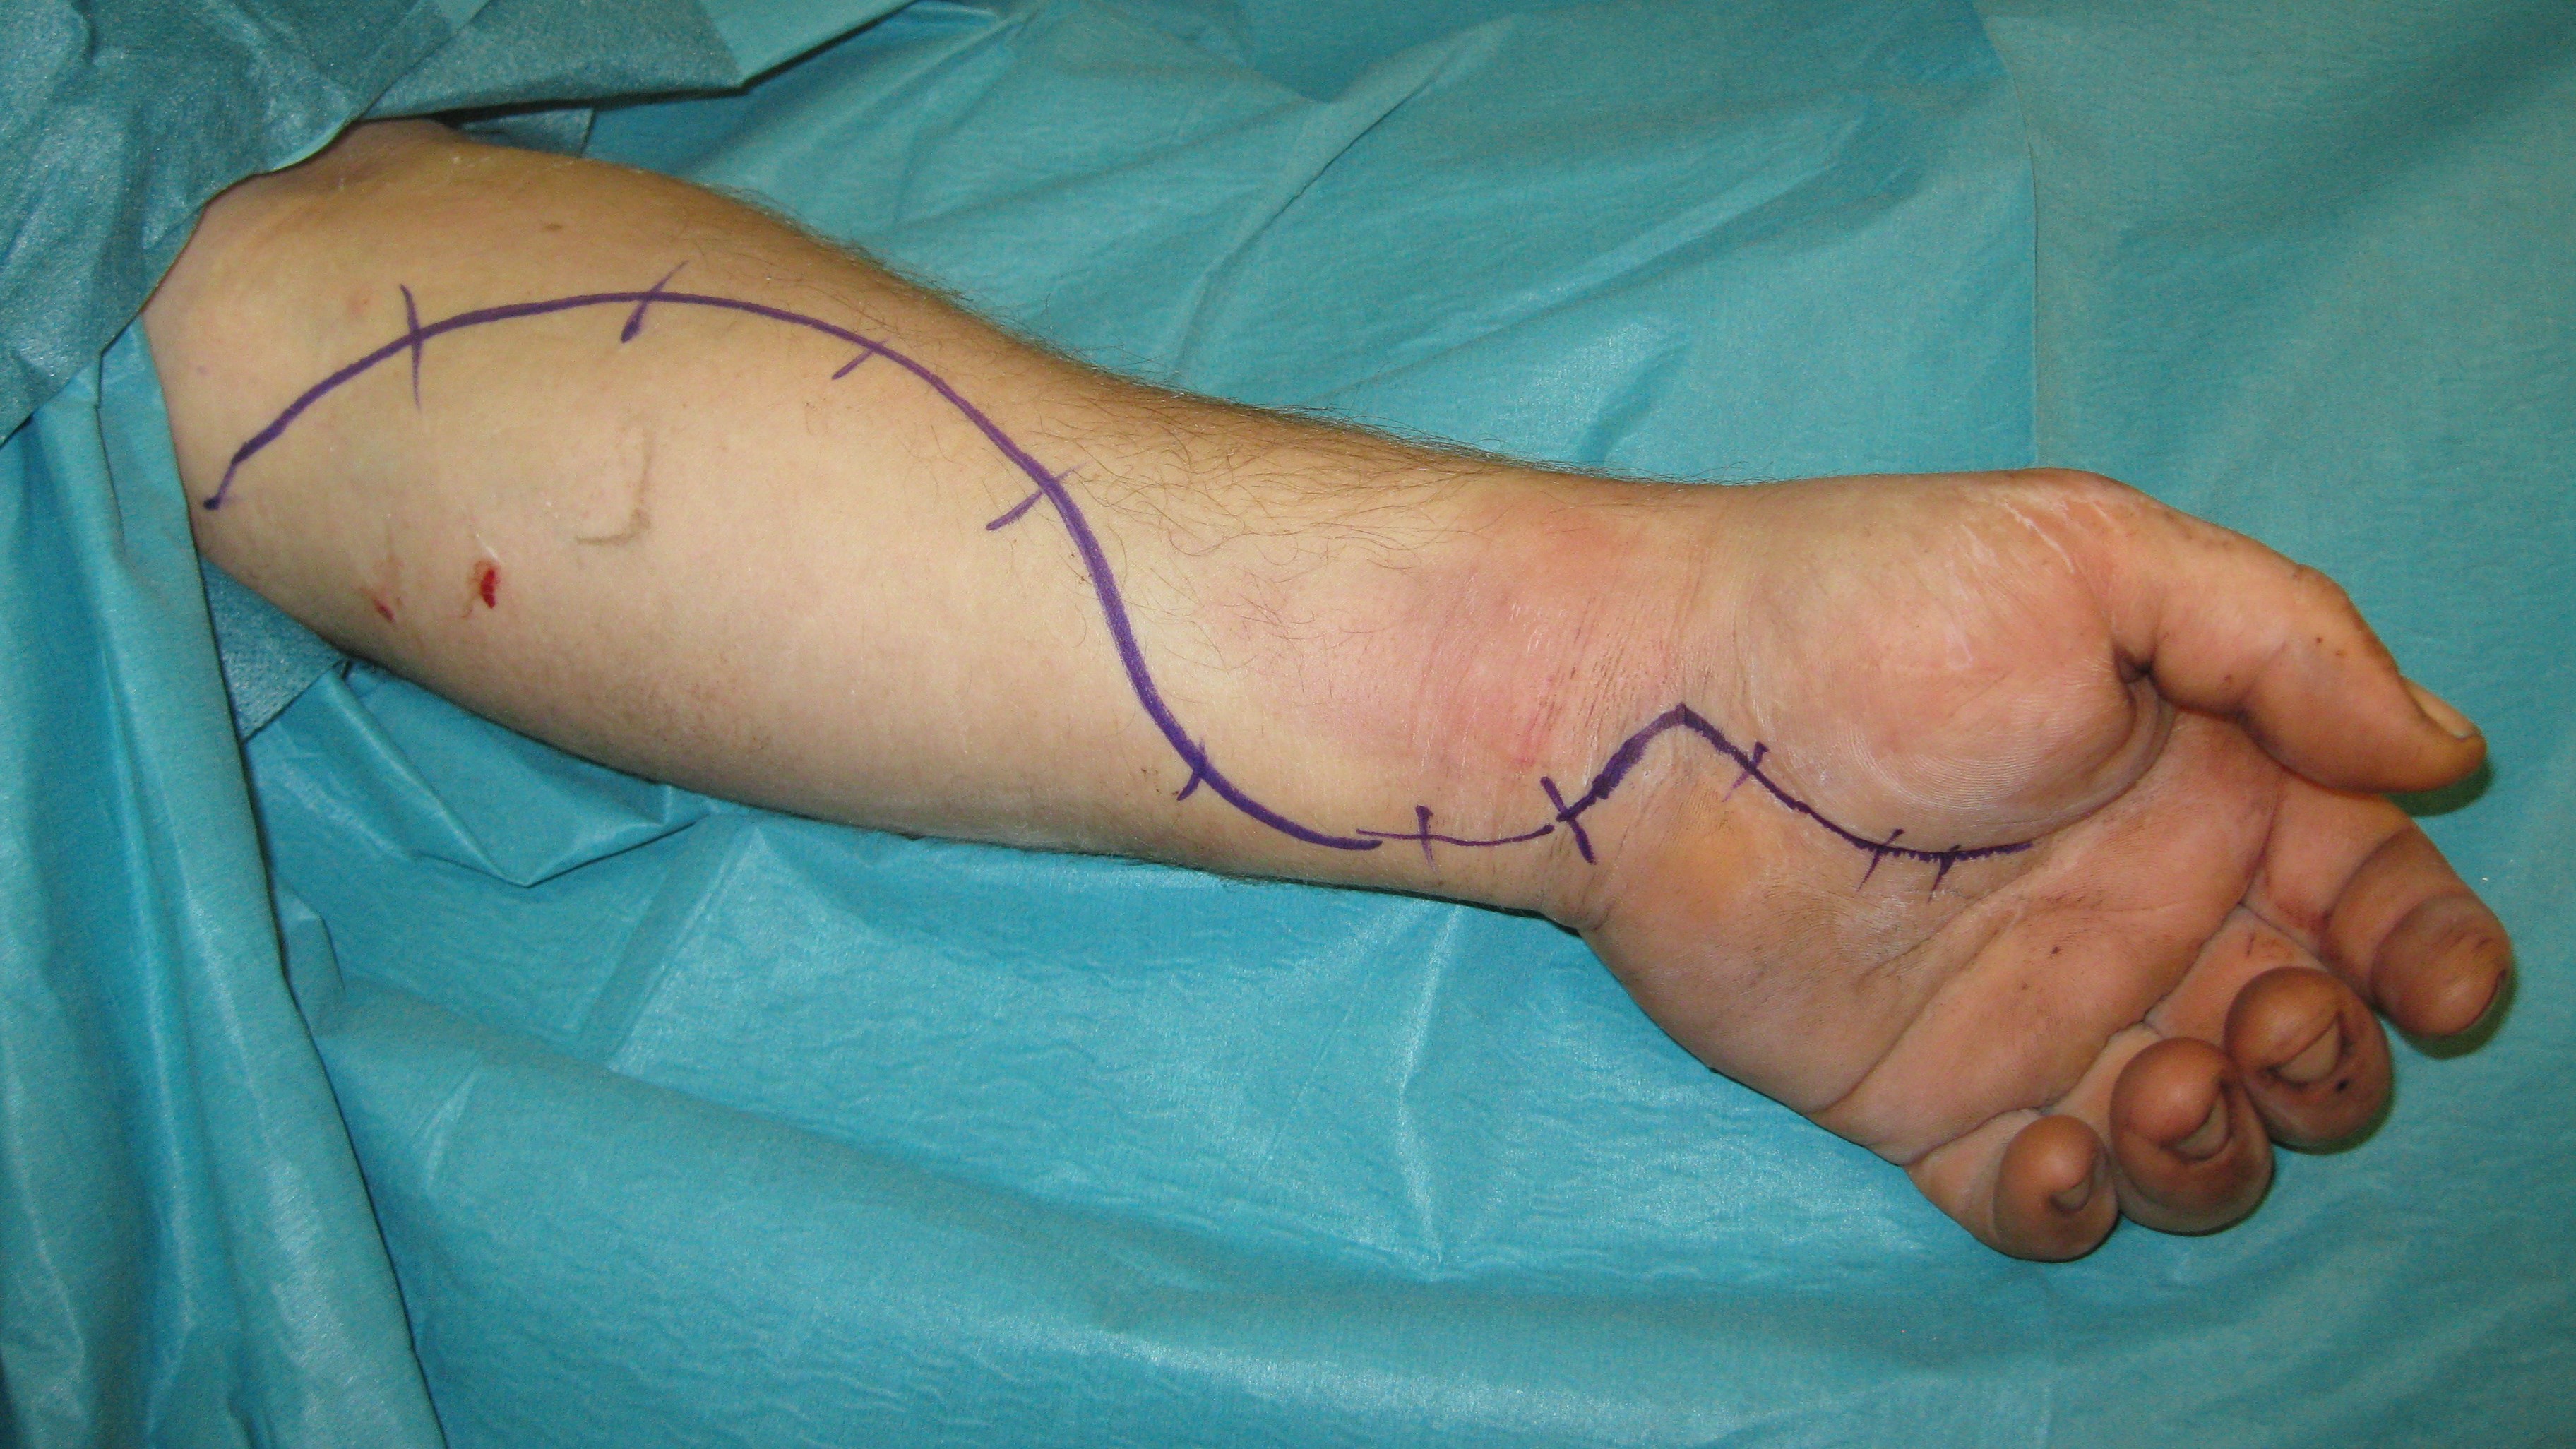

Kompartmentsyndrom

Allmänt

Kompartment syndrom är ett tillstånd där trycket inom ett avgränsat rum överstiger det kapillära perfusionstrycket. Genomblödning av muskler och andra vävnader inom detta kompartment upphör då vilket leder till vävnadsnekros. Observera att det är perfusionstrycket på kapillärnivå som är avgörande. Därför är palpabla pulsar ingen garanti för att det inte föreligger kompartmentsyndrom.

Kompartmentsyndrom är ett urakut tillstånd eftersom det kan räcka med några timmars nedsatt cirkulation för att irreversibla skador skall uppkomma. Det är i första hand muskulaturen som tar skada. Sådana skador medför i ett längre perspektiv till fibros och kontraktur vilket leder till svårbehandlad felställning och stelhet.

Den primära orsaken är ofta en klämskada, ett slag eller ett yttre tryck. En inte ovanlig orsak är att en medvetslös eller kraftigt berusad person har legat och tryckt med huvudet mot underarmen. Det kan också vara en fraktur eller inre blödning som är orsaken till att trycket ökar. När trycket ökar kan skada uppstå som i sin tur ger ökad cellpermeabilitet vilket leder till ödem som i sin tur ökar trycket och en självgenererande ond cirkel uppkommer.

Behandling

Behandlingen är att det avgränsade rummets väggar, dvs. att fascior öppnas kirurgiskt. Många gånger sväller då musklerna fram och huden kan inte slutas. Man får då dra ihop såret så gått det går utan för mycket spänning för att sedan sluta såret när musklerna svällt av. Det finns även teknik för att hålla ihop och successivt sluta sårkanterna mha av ståltråd eller elastiska band.

Hudtransplantat kan senare behövas. När det gäller underarmen finns tre kompartment och både extensor och flexormuskulatur kan drabbas. I handen finns ett tiotal slutna kompartment som alla måste öppnas kirurgiskt om kompartment syndrom misstänks i denna region.